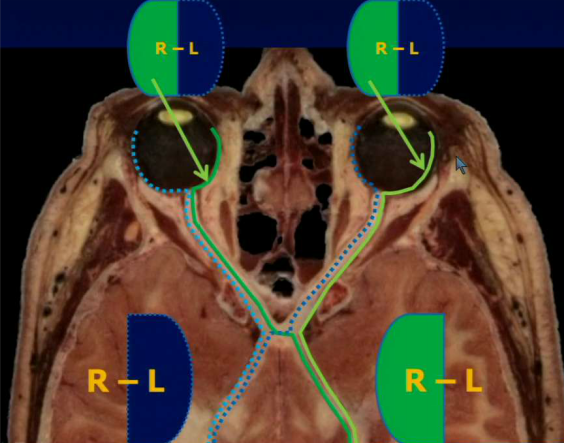

Which part of the eye field is seen by the right occipital lobe? The left?

The right occipital lobe sees the left half of the eye field in each eye and the left occipital lobe sees the right half of the eye field in each eye.

A patient presents complaining that she can never see their kids sneaking up on the side of her. Where in the optic tract does she have a lesion?

Optic chiasm. She has bitemporal hemianopsia. Remember that the image coming from the temporal nerve transmits stimuli from the nasal field.